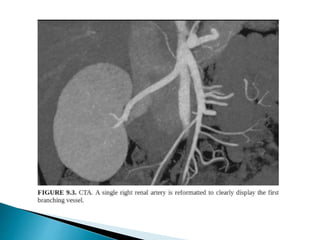

 CT is the preferred imaging due to better spatial resolution

and sensitivity to vascular calcifications and renal stones.

 CTA >> MRA

1. Distinguishing single/two main renal arteries.

2. Anatomy and to identify the point at which first branch

occurs.

3. Renal venous anatomy,

4. Tiny polar accessory arteries.

 Variant anatomy

◦ accessory renal arteries:

◦ aberrant renal arteries: enter via the renal capsule rather than the

hilum

◦ early branching (or prehilar branching):

 occurs within 1.5-2.0 cm of origin in the left renal artery or in

the retrocaval segment of the right renal artery

 important to recognize in renal transplant for successful

anastomoses